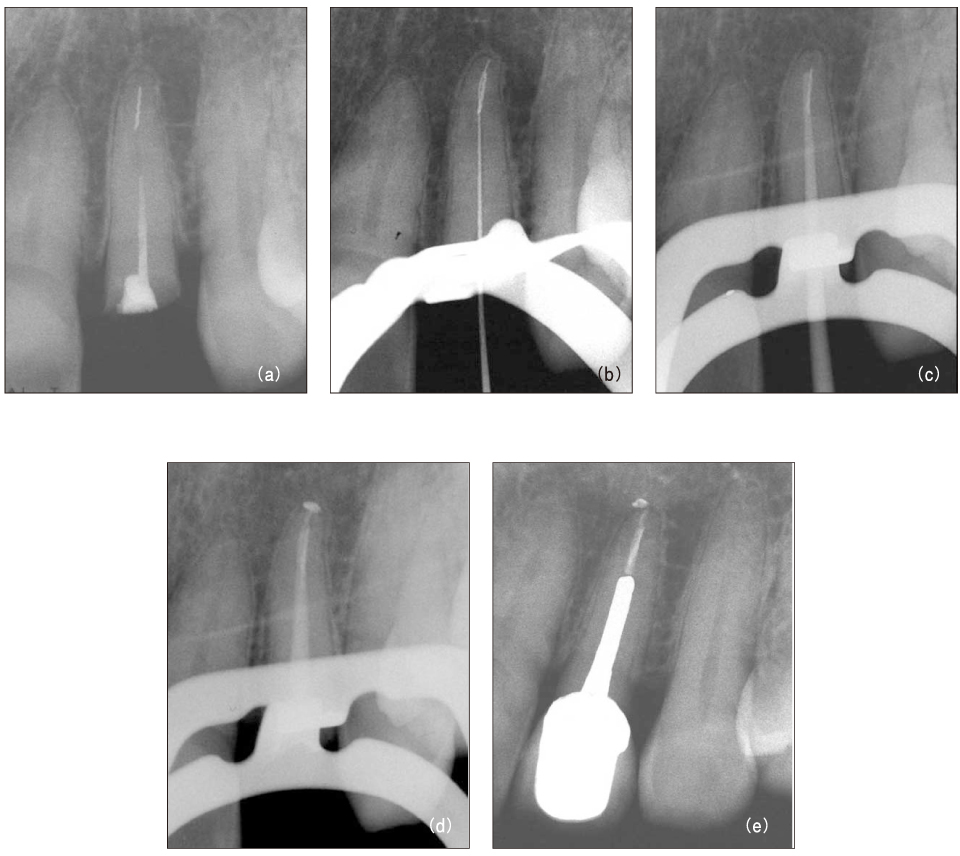

Figure 3

File separation in the root canal (a, b) and remove using ultrasonic device under microscope (c).

Figure 3 File separation in the root canal (a, b) and remove using ultrasonic device under microscope (c).